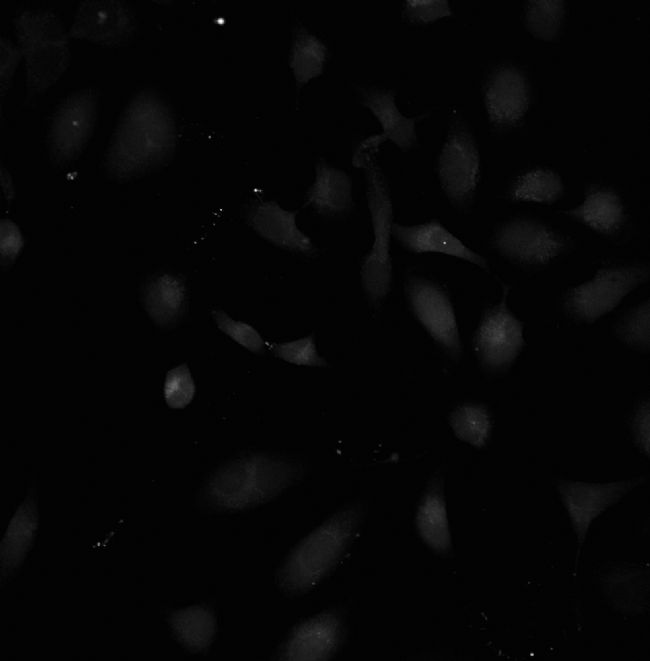

YOKOGAWA的雙轉(zhuǎn)盤共聚焦高內(nèi)涵系統(tǒng),實現(xiàn)了高通量的共聚焦成像及定量分析統(tǒng)計,可準(zhǔn)確定量β-淀粉樣蛋白聚集體(ASPD)在興奮神經(jīng)元中的聚集水平(圖6)及ASPD對鄰近NAKα3神經(jīng)元的殺傷作用(圖7)。

圖7. ASPD具有神經(jīng)毒性,導(dǎo)致NAKα3陽性神經(jīng)元細胞死亡